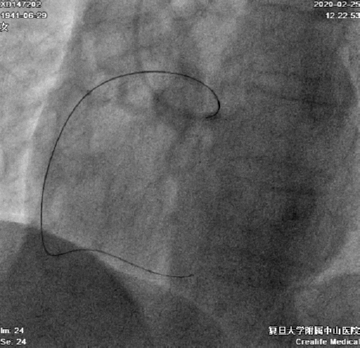

送入Tazuna 1.25*10mm、Artimes 1.0*10mm小球囊,支撑力不够,Transporta GE回弹(图8)

图8

用Sprinter 2.0*15mm、Tazuna 2.5*20mm球囊连续高压序贯扩张右冠近中段多次,此后小球囊顺利通过RCA中段闭塞段(图9-10)

图9

图10